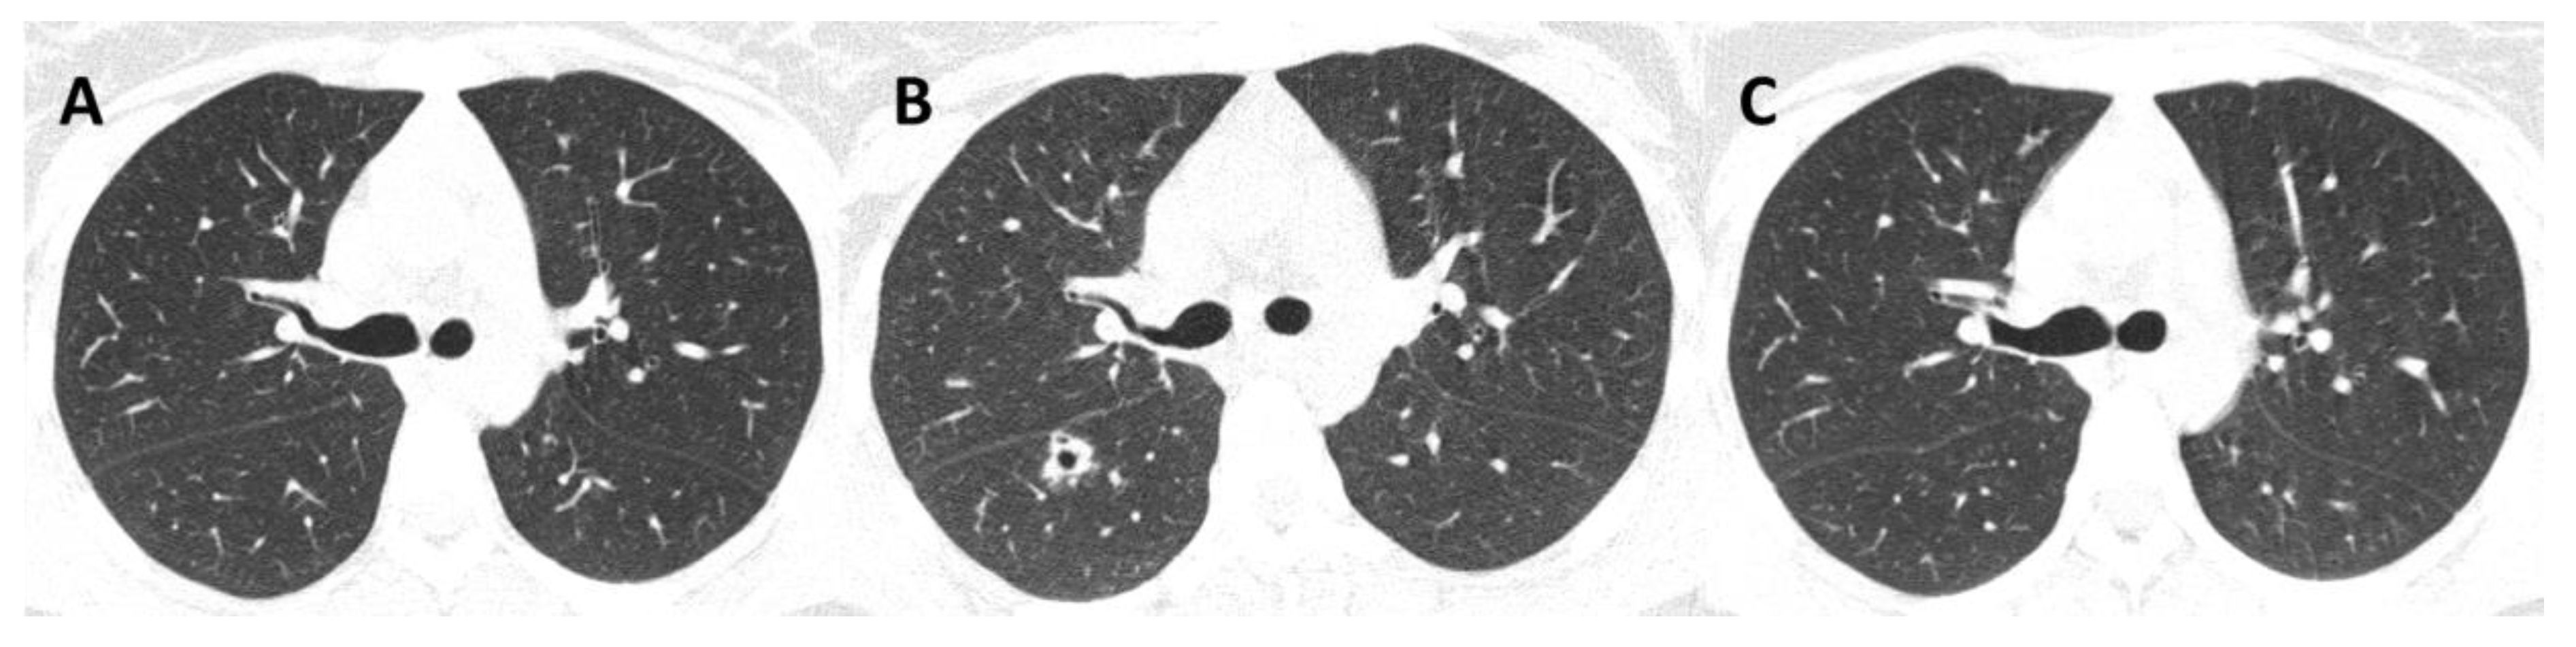

3.3. Radiological Patterns

| 1 (2018) | Male | 71 | None | Primary pulmonary | Lungs | Alcoholism COPD | No | Reticulonodular infiltrate; cavitation; fibrosis Unilateral/Multilobar | Sputum; BAL | ITZ; PSZ | Under treatment |

| 2 (2018) | Male | 63 | Contact with cat | Disseminated | Lungs, bone | Alcoholism COPD | No | Cavitation; fibrosis; hilar lymphadenopathy Unilateral/Unilobar | Sputum; BAL | ITZ; AmB; PSZ | Under treatment |

| 13 (2013) | Male | 43 | Scratched by diseased cat | Disseminated | Skin, bones, upper airways | HIV (CD4 = 35 cells/mm3) Alcoholism | Tuberculosis | Diffuse reticulonodular infiltrate; calcified nodules, fibrosis | Sputum | ITZ; TBF; AmB; PSZ | Death |

| 14 (2018) | Female | 20 | Contact with diseased cats | Disseminated | Skin, lungs, bones, upper airways | HIV (CD4 = 56 cells/mm3) Alcoholism | Pneumocystis pneumonia | Cavitation; reticulonodular infiltrate; consolidation | Sputum | ITZ; AmB; PSZ | Cure |